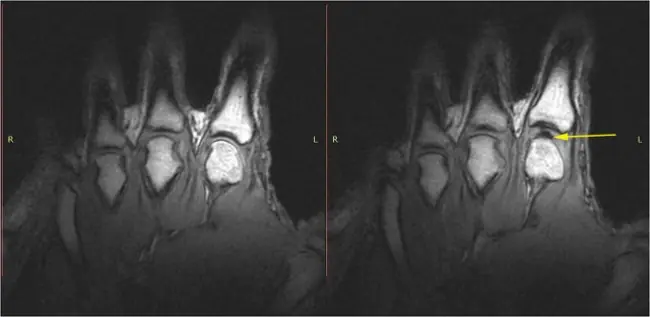

Al manipular tus dedos el espacio entre las articulaciones crece, por lo que los gases que se disuelven en el líquido sinovial (líquido que cubre y protege a las articulaciones) forman burbujas.

Cuando las pequeñas burbujas se unen, forman otras de mayor tamaño, que ”revientan“ cuando entra más fluido entre esos espacios abiertos. El “tronar” los dedos solamente puede ser repetido pasados 15 minutos, que es el lapso en que la articulación se reincorpora a su tamaño normal y los gases son disueltos en el líquido sinovial.